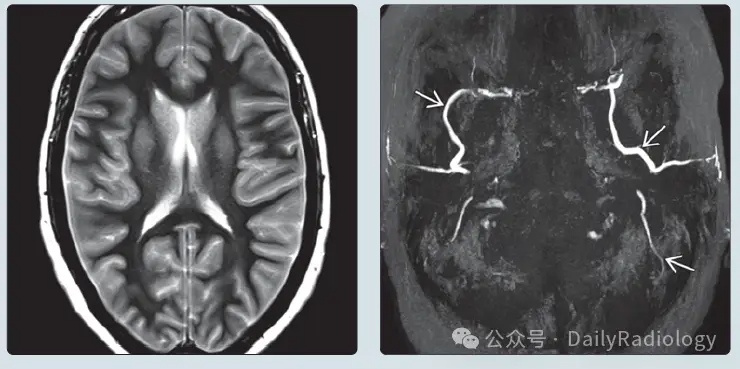

(左图) 50岁女性脑死亡患者濒死前轴位T2加权成像 (T2WI):脑室狭小,脑回肿胀,脑沟近完全消失。

(右图) 同例患者颏下顶位MRA最大密度投影 (MIP):仅见 颈外动脉分支 血流信号,颅内血管无显影。